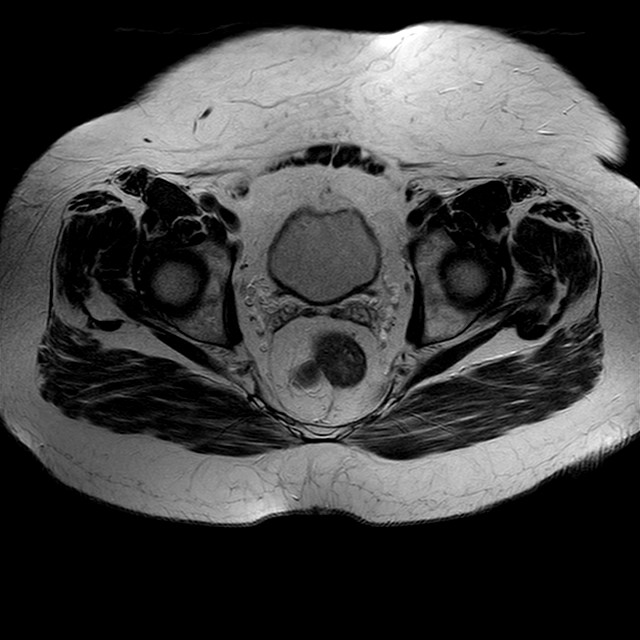

Esami: RMN BACINO

eT2w TSE

Evidenti e simmetriche alterazioni osteofitosiche in regione coxo femorale con riduzione delle rime articolari. Degenerazione completa del cercine glenoideo. Non attuali segni di versamento articolare. Non segni di edema osseo che escludono attuale algodistrofia od osteonecrosi. Lieve e simmetrica riduzione del trofismo della muscolatura glutea.